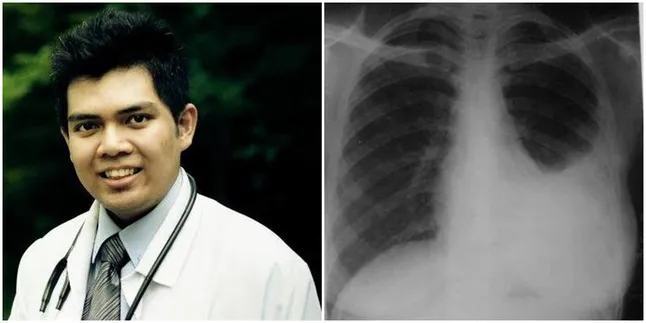

Seorang dokter asal Malaysia, Mohd Syamirulah Rahim, melalui akun Facebooknya membagikan satu kisah tragis seorang pasien perokok yang dia tangani. "Kita namakan saja dia sebagai Ali, tentu bukan nama sebenarnya," tulis dokter tersebut pada Rabu (23/08) lalu.

Begitu masuk rumah sakit dan menjalani serangkaian pemeriksaan, Ali tidaklah terjangkit Tuberkulosis atau asma seperti dugaan dokter sebelumnya. Dari hasil rontgen diketahui bahwa ternyata paru-paru Ali telah berisi cairan, pemuda berusia 24 tahun yang bekerja sebagai kuli ini terjangkit Empyema Paru-Paru. Kondisi yang dialami Ali menyebabkan penumpukan cairan berupa nanah di pleura karena banyaknya bakteri yang tertimbun di sana.Â

"Dokter segera mengambil tindakan untuk mengeringkan paru-paru Ali dengan mengeluarkan cairan tersebut. Apabila jarum ditusuk ke rongga pleura Ali, cairan berwarna putih kekuningan keluar. Nanah, ya nanah," lanjut dokter Syamirulah.